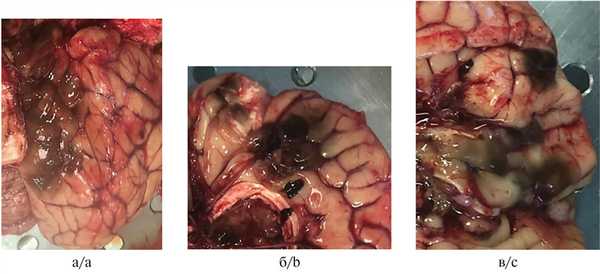

Во время проведения аутопсии при исследовании головного мозга в мягких мозговых оболочках обнаружены уплотненные очаги темно-коричневого цвета с нечеткими краями, частично сливающиеся между собой (рис. 2). На горизонтальном разрезе выявлена инвазия образования в кору головного мозга.

Рис. 2. Пигментные многоочаговые образования в мягких мозговых оболочках головного мозга, результаты аутопсии.

а — затылочная доля правого полушария головного мозга; б — медиальная поверхность лобной доли правого полушария головного мозга; в — базальная поверхность лобной доли левого полушария головного мозга.